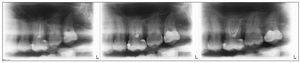

La opción de gran formato permite visualizar áreas más amplias. Por consiguiente, las imágenes longitudinales se utilizan cuando las radiografías intraorales no son suficientes por su pequeño formato (figs. 6 a 8).

Figura 6. Visualización deficiente del ápice radicular tras la apicectomía del diente 46.

Figura 7. Visualización completa y sin distorsiones con cortes estrechos longitudinales para el control de la apicectomía del diente 46.

Figura 8. Conductos radiculares obturados con una imagen radioopaca debida a una lesión poliposa basal del seno maxilar.